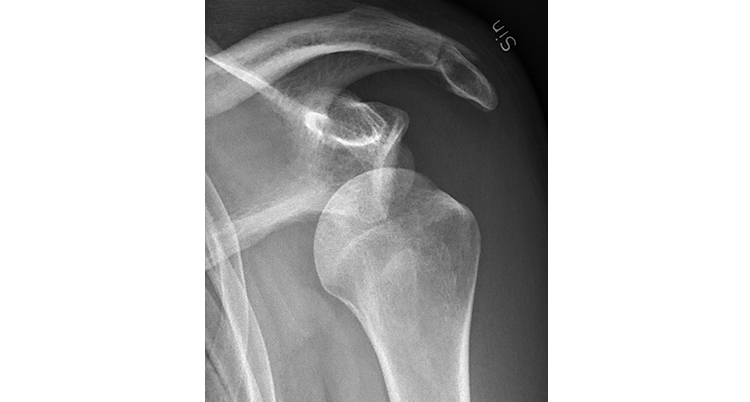

Shoulder dislocation, anteroposterior view before reduction. Doc. Riche, Wikimedia Commons, 2018. Licensed under CC BY-SA 4.0.

Shoulder Instability and Dislocations

What is it: The shoulder joint relies heavily on muscles, ligaments, and connective tissue for stability. Shoulder instability occurs when these structures are unable to keep the joint centered during movement. This can happen after a traumatic injury, such as a fall or sports collision, or it can develop over time with repetitive overhead activity.

Symptoms: Symptoms may include a feeling that the shoulder is loose or slipping, pain with certain arm positions, or a history of the shoulder partially or fully dislocating. Some people feel apprehensive or unstable during specific movements.

What to do: Physical therapy is often the first step in treatment and focuses on strengthening the muscles that stabilize the shoulder, improving coordination, and restoring confidence with movement. Early rehabilitation after a dislocation can significantly reduce the risk of future instability episodes.